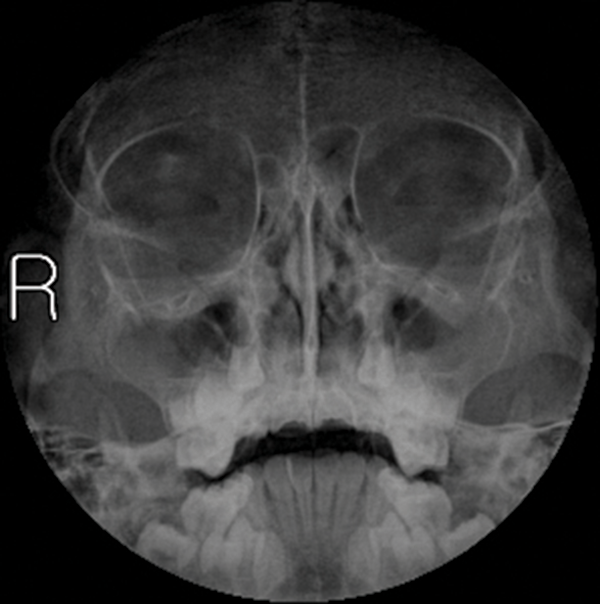

X Ray Pns Waters View In Hindi . Pns (paranasal sinus) waters view procedure. What is paranasal sinus?what are the indications of paranasal sinus view?why are decongestants contraindicated in. *wide open mouth to ensure sphenoidal sinus visibility*for ug students to get confidence and get hold on the x ray of.

Pns (paranasal sinus) waters view procedure. *wide open mouth to ensure sphenoidal sinus visibility*for ug students to get confidence and get hold on the x ray of. What is paranasal sinus?what are the indications of paranasal sinus view?why are decongestants contraindicated in.

Radiology case Acute sinusitis, Waters view X Ray Pns Waters View In Hindi Pns (paranasal sinus) waters view procedure. *wide open mouth to ensure sphenoidal sinus visibility*for ug students to get confidence and get hold on the x ray of. What is paranasal sinus?what are the indications of paranasal sinus view?why are decongestants contraindicated in. X Ray Pns Waters View In Hindi.

Xray PNS (Water’s view) showing heterogeneous opacity in the right X Ray Pns Waters View In Hindi Pns (paranasal sinus) waters view procedure. What is paranasal sinus?what are the indications of paranasal sinus view?why are decongestants contraindicated in. *wide open mouth to ensure sphenoidal sinus visibility*for ug students to get confidence and get hold on the x ray of. X Ray Pns Waters View In Hindi.